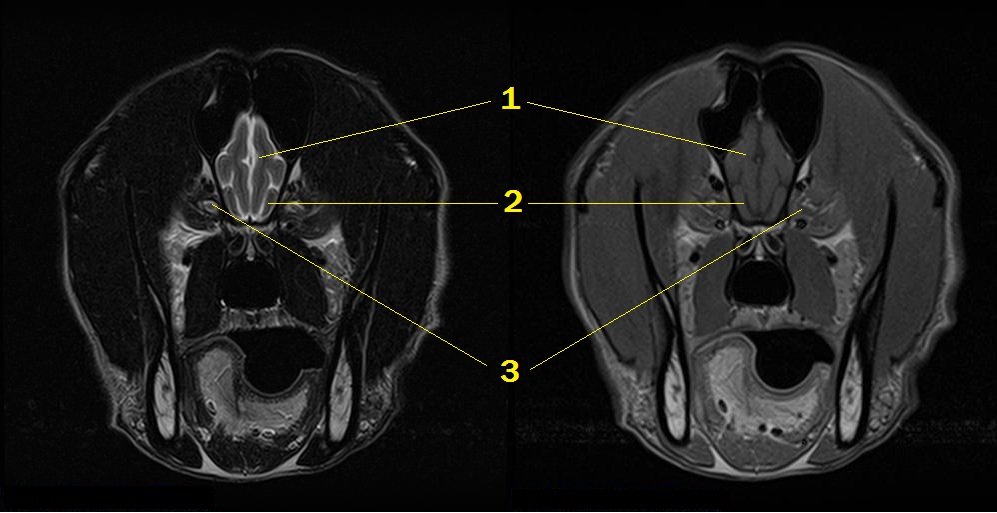

Q. Identify the structures labeled below:

1. frontal lobe

2. olfactory peduncle

3. optic nerve